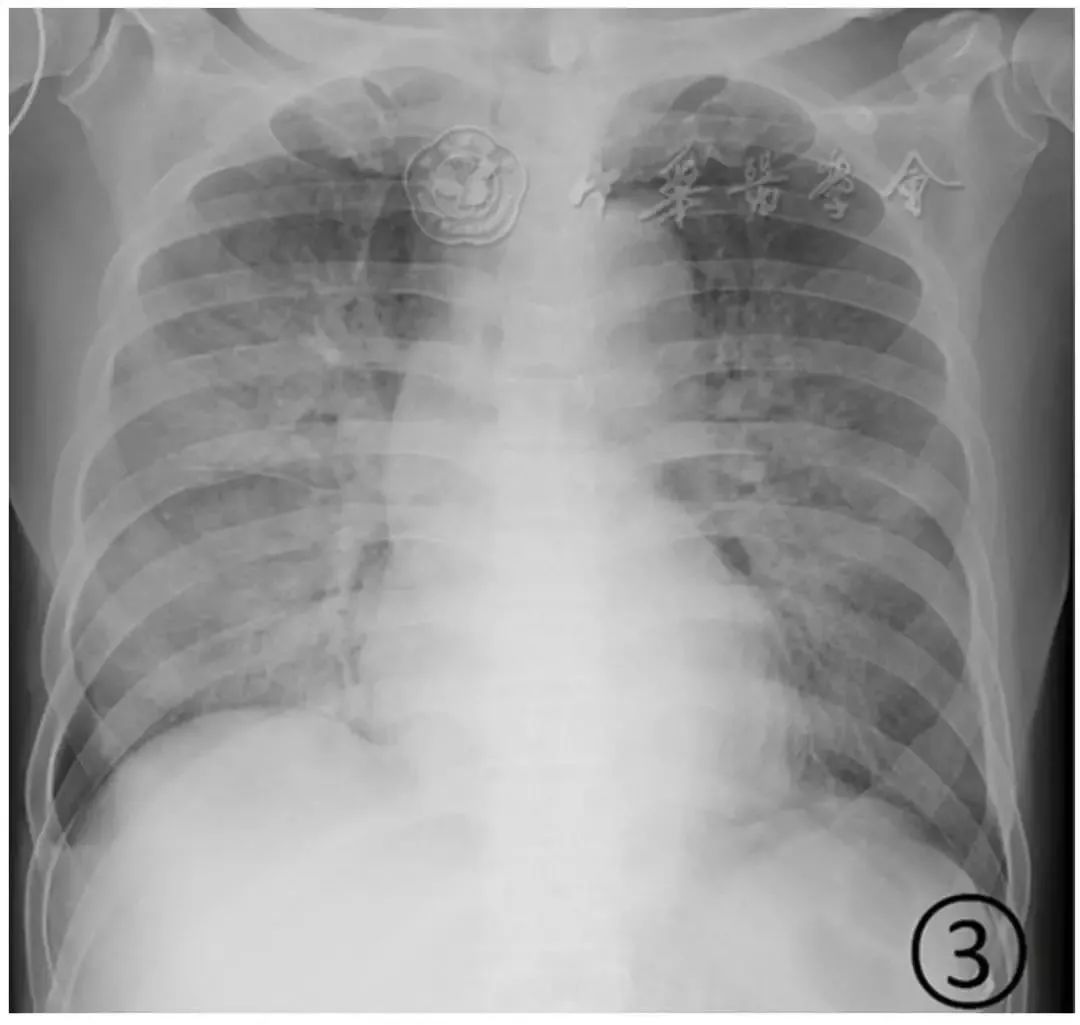

图3 男,69岁,新型冠状病毒感染的肺炎。胸部平片显示双肺大片状磨玻璃阴影,右侧为著,其内纹理增粗;右侧水平叶间胸膜部分轻度增厚,右肋膈角变钝,提示少量胸腔积液

重型患者双肺多发实变影,部分融合成大片状实变,可有少量胸腔积液(图3)。病变进展为危重型,表现为两肺弥漫性实变阴影,呈"白肺"表现(图4),可以伴有少量胸腔积液。